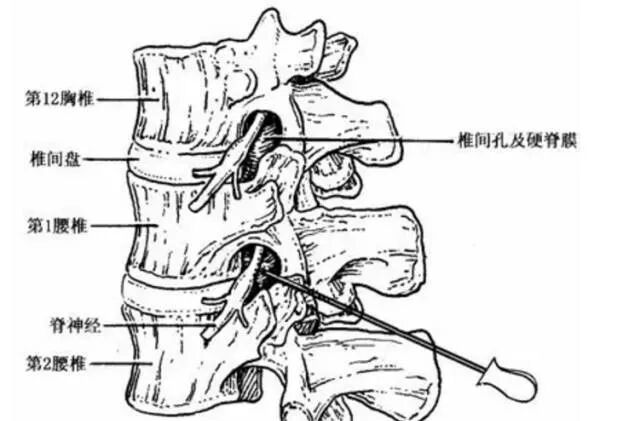

(3)椎管造影:常在腰2,3椎间隙穿刺注药造影,此时可出现尖形中断,梳状中断及蜂腰状改变,基本上可了解狭窄全貌(图3),由于本检查属侵入式,目前已少用。

4、硬膜外封闭:

这个治疗是一种往腰椎神经根受压部位直接注射止疼、消炎药的一种方式。因为作用比较直接,如果诊断正确,注射精准,效果往往非常好。有很多人打完之后症状会很快缓解或消失。

另外,硬膜外封闭注射,除了是一种有效的治疗方式外,还是一种有效的诊断方式,用这种方式,可以明确我们之前的诊断是否正确。